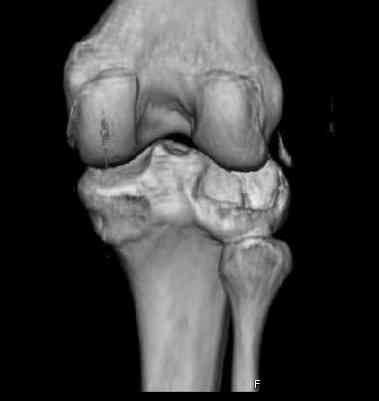

Остеосинтез при импрессионном переломе заднего отдела наружного мыщелка tibia? |

Здравствуйте, уважаемые коллеги!Подскажите, пожалуйста, какой выбрать доступ и способ фиксации при импрессионном переломе заднего отдела наружного мыщелка большеберцовой кости. Женщина 40 лет, травму получила 02.01.2008, катаясь на горных лыжах.Есть ли здесь необходимость использовать задний доступ, или можно справиться через наружный? Есть ли шансы сделать закрыто - под ЭОП через медиальное "окошко" поднять забойником суставную поврехность? Какой лучше использовать фиксатор?Спасибо.

центральная импрессия, а при ипрессии с краевым переломом - после приподнимания импрессии опорная (Butress) пластина, как на снимке.